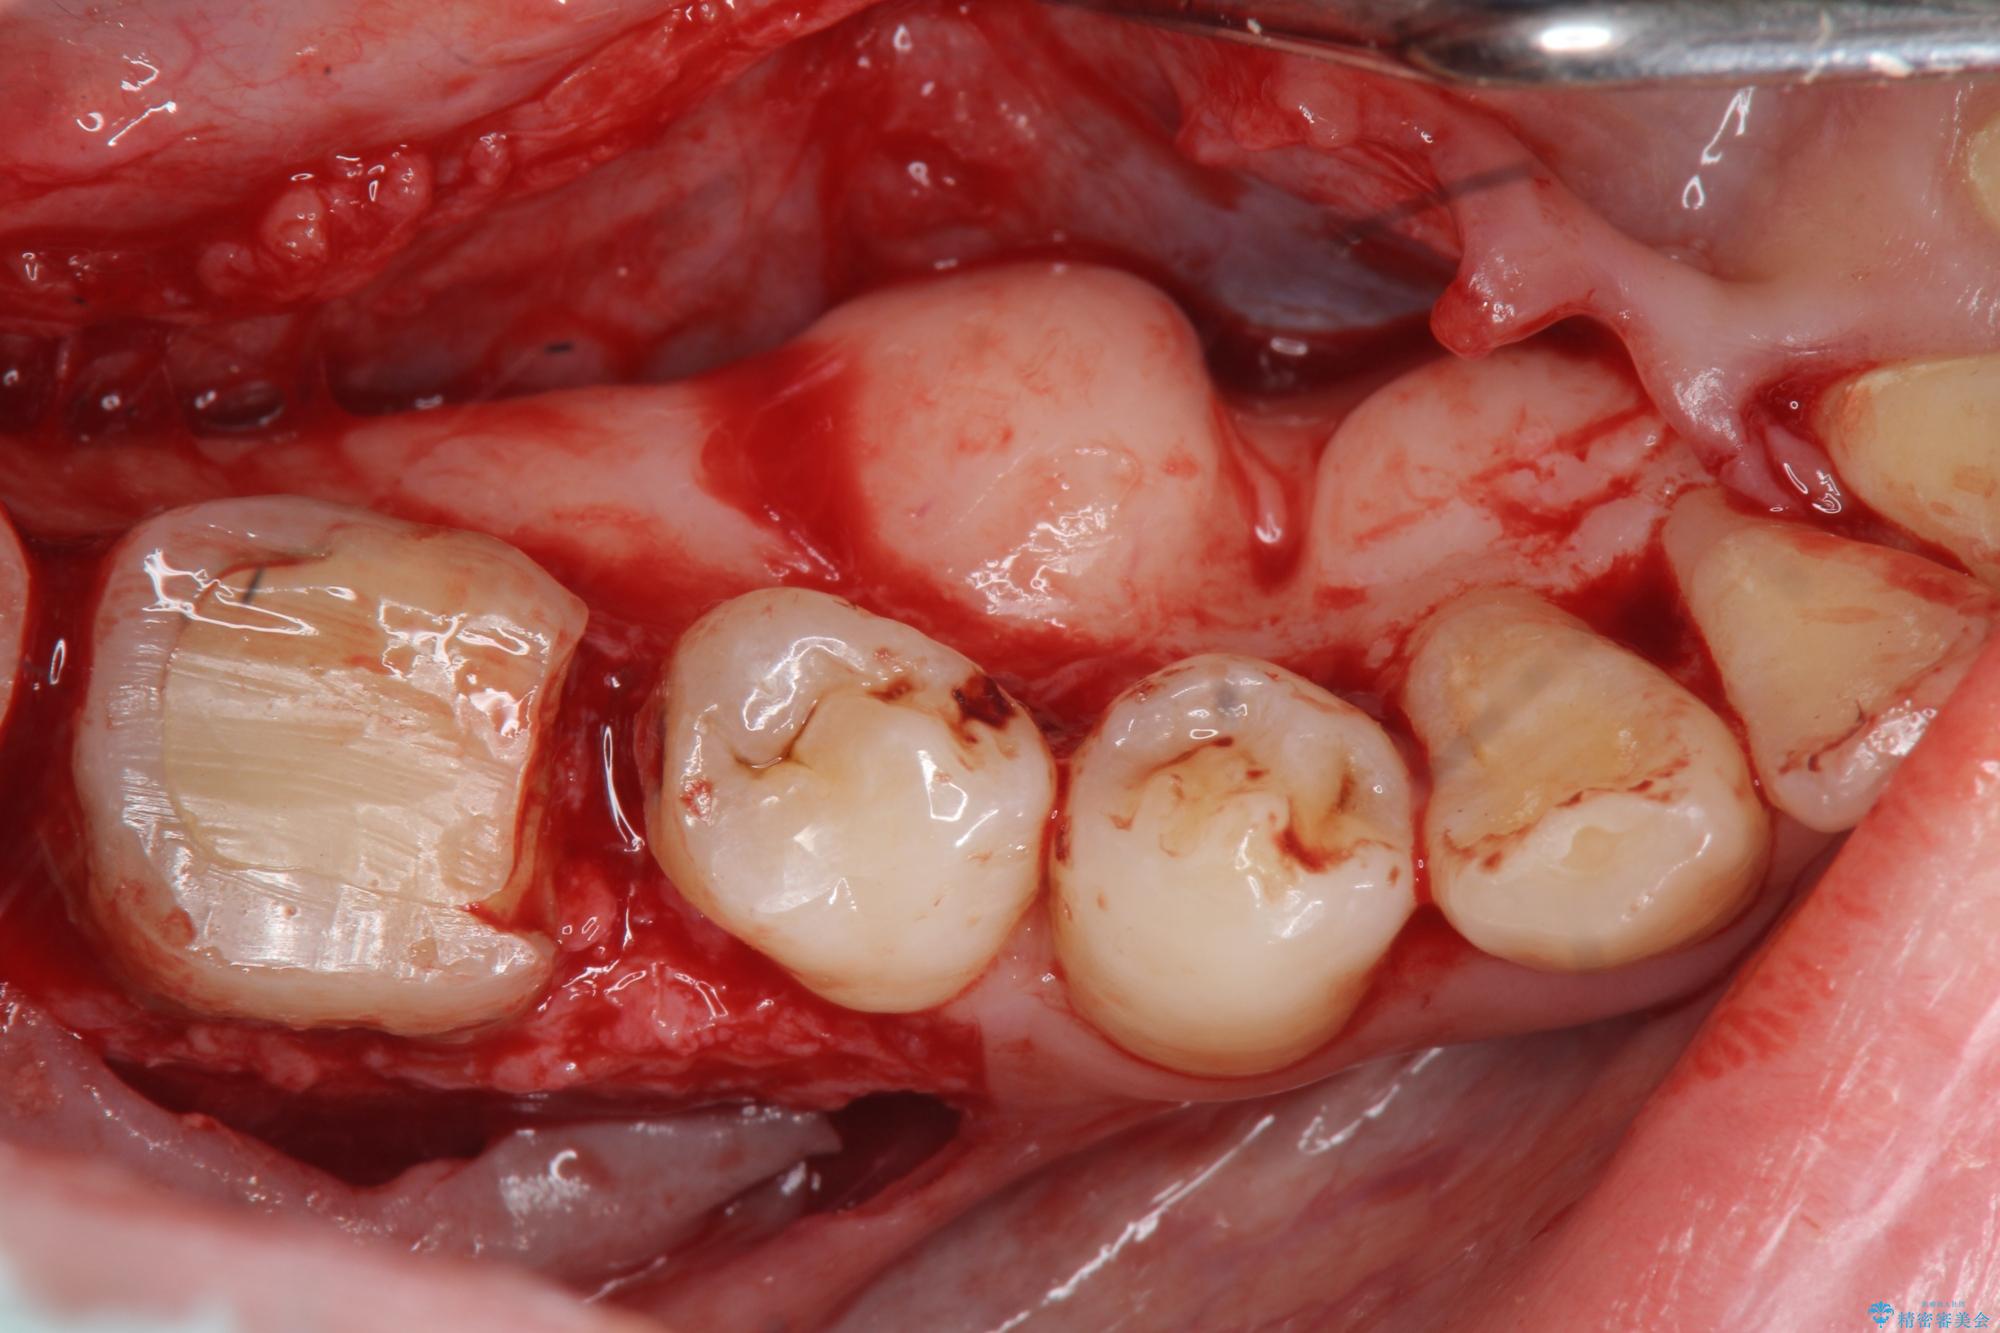

奥歯は既に根管治療が為されクラウンを装着する必要性がある状態ですが、歯の高さが低くクラウンの安定性・強度を担保するために歯周外科を行う治療計画としました。

歯周外科を行うことで、歯ぐきの位置を下げ歯の高さを作り出し安定したクラウンの装着が可能となります。また同時に舌の邪魔となっていた骨隆起の除去を行うこととしました。